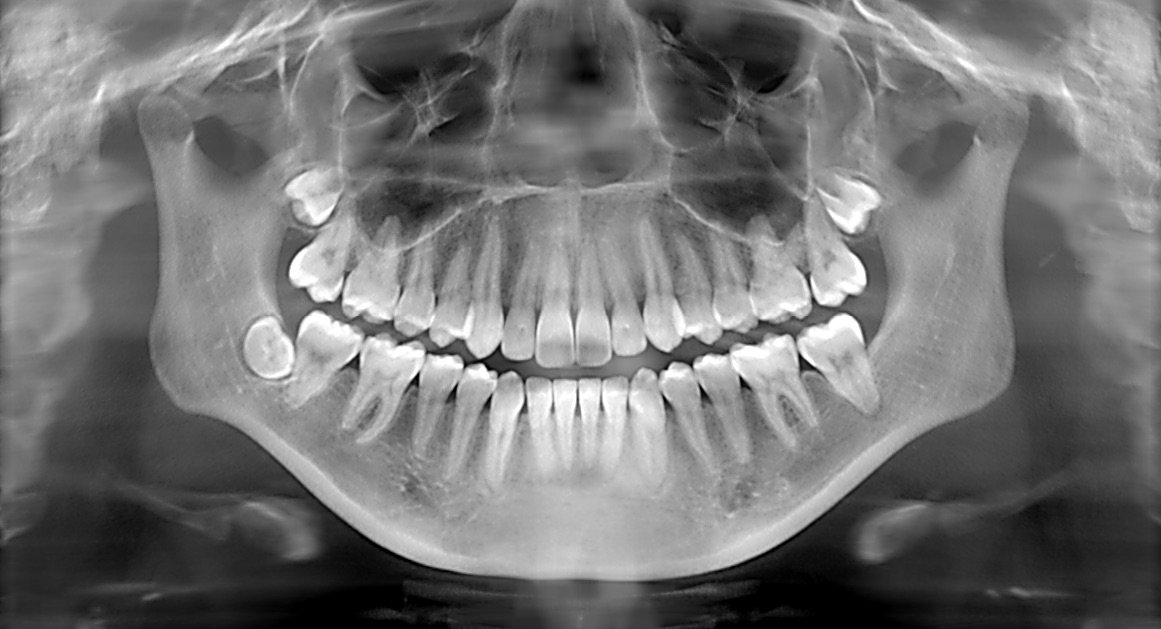

Enter the world of precision diagnostics with dental X-rays, a tool that promises to change the narrative for individuals like Priya. These X-rays are more than just images; they are a gateway to understanding the hidden intricacies of oral health.

Imagine Priya’s relief when she learned that a simple, non-invasive dental X-ray could unveil the root cause of her discomfort. With precision diagnostics, dentists can see beyond the surface, identifying cavities, bone loss, and even tumors that are invisible to the naked eye. For Priya, this meant a tailored treatment plan that addressed her specific needs, minimizing unnecessary procedures and maximizing her comfort and health.

Such stories underscore the importance of regular dental check-ups and the role of modern diagnostics in proactive health management. Precision diagnostics with dental X-rays not only solve the immediate problem of accurate detection but also empower individuals to take control of their oral health with confidence and peace of mind.